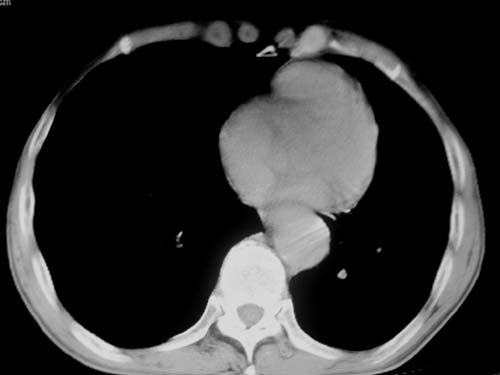

标题: CT19736:男,76岁,咳嗽,胸痛 [打印本页]

标题: CT19736:男,76岁,咳嗽,胸痛

支持左上肺周围型肺癌性并空洞形成伴胸椎转移。

考虑癌性空洞并胸椎转移。

左上肺癌性空洞伴胸椎转移。